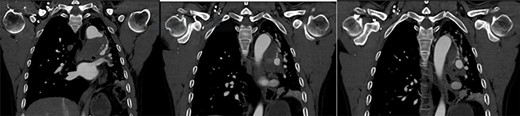

On presentation, chest X-ray illustrated a prominent proximal descending thoracic aorta contour and a completely collapsed left lung (Fig. 1). On computed tomography angiogram (CTA), the patient was found to have a large saccular aneurysm measuring 5.0 × 5.0 × 5.0 cm in size, arising from a focal location of the proximal descending thoracic aorta distal to the origin of the left subclavian artery with evidence of contained rupture (Fig. 2). The mass was found to be causing significant external compression of the left main bronchus leading to significant effacement of the left main primary bronchi leading to extensive collapse in both left upper and lower lobes and overall reduction in volume of the left hemithorax (Fig. 3).